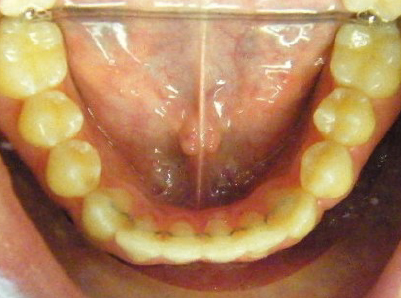

Early Phase of Treatment Examples

Patient 4: Crossbite due to thumb sucking.